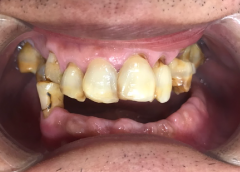

Anh Nguyễn Tấn Dũng

• Tiêu xương hàm và mất gần hết răng

Việt Kiều Mỹ

Trước đây, anh Dũng từng bọc răng sứ nhưng bị viêm nha chu và nhiễm trùng nặng, dẫn tới hàm răng lung lay và gãy rụng chỉ còn vài chiếc.

Qua thăm khám kỹ lưỡng của bác sĩ Thái còn thấy được xương hàm của anh đã bị tiêu khá nhiều. Do đó, để đảm bảo khả năng ăn nhai và sức khỏe cho anh, bác sĩ Thái đã chỉ định nhổ các răng lung lay nặng và cấy ghép Implant All On 4. Với 4 trụ Implant giúp khôi phục toàn hàm răng mất và kích thích xương hàm phát triển.

Nhờ bác sĩ Thái chỉ định đúng phương pháp trồng răng và tiến hành điều trị kịp thời, anh Dũng đã phục hồi lại hàm răng chắc khỏe, ăn nhai tốt và cải thiện thẩm mỹ hoàn hảo.